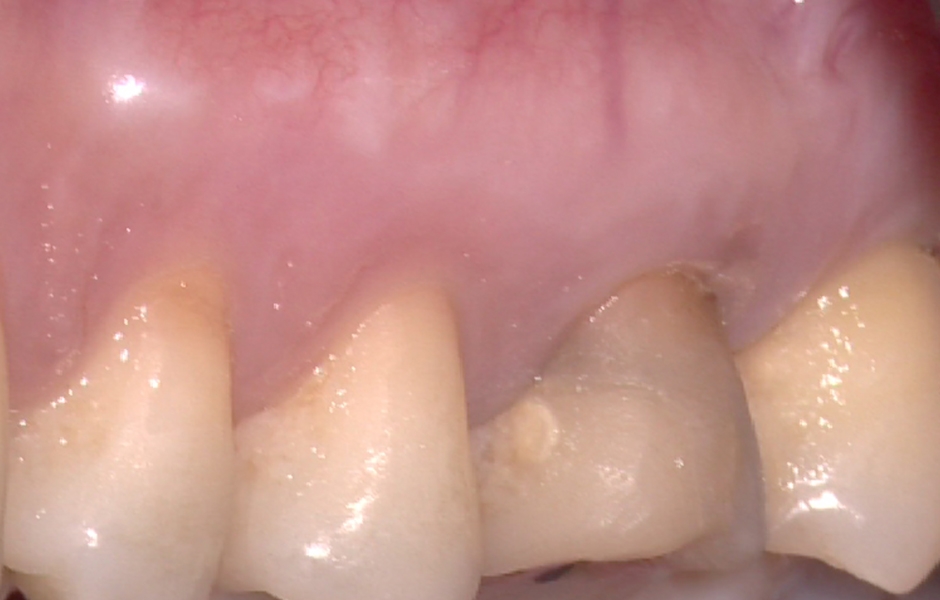

Obr. 1.2: Submarginální incize.

Obr. 1.5: Odstranění sutur po 48 hodinách a kontrola po třech letech – kompletní absence jizvy.

Obr. 4.2: Submarginální lalok.

Obr. 4.7: Odstranění sutur po 48 hodinách a kontrola po třech letech prokazující kompletní absenci jizvy.